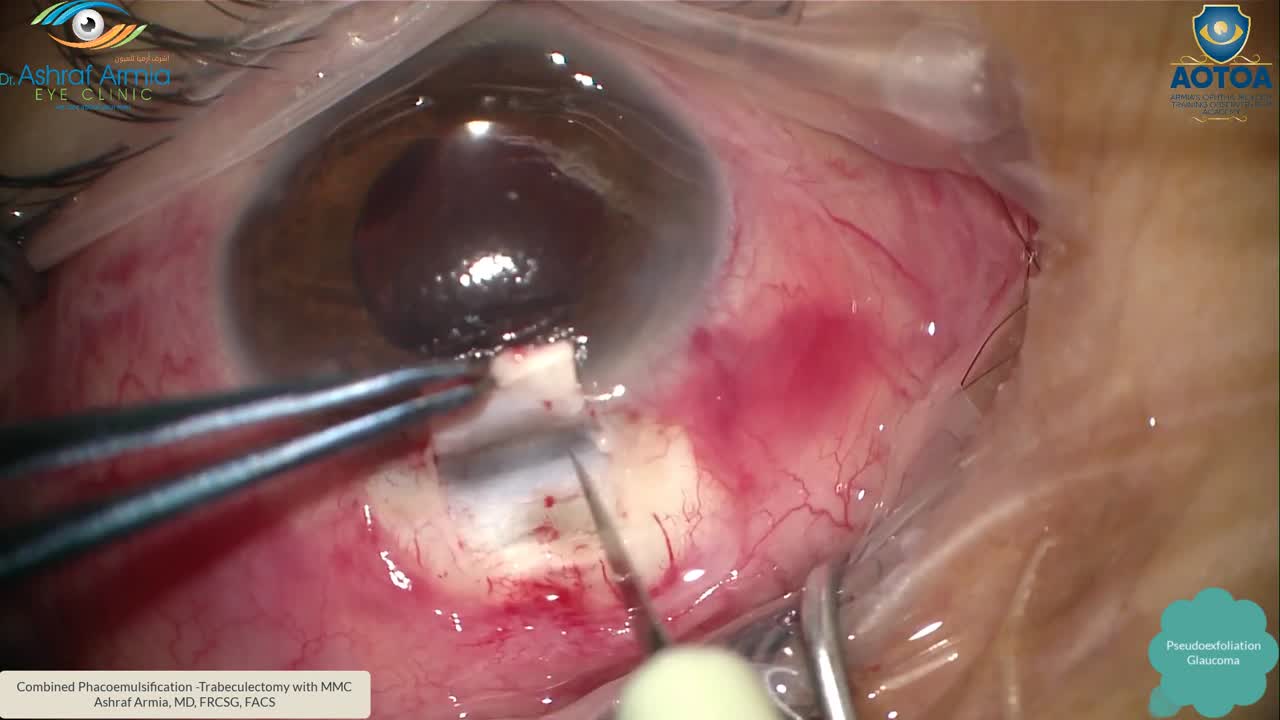

<섬유주 절제술과 누공, sclerotomy>

섬유주절제술에서 방수가 빠져나가는 구멍은 누공(sclerotomy)입니다.

누공의 안구외부는 결막아래공간(subconjunctival space)이며,

누공의 안구내부는 섬유주소대(trabecular meshwork) 부근입니다.

누공의 안구외부부분은 결막 아래공간에서 공막절편(scleral flap)에 의해서 덮여있는데,

이부분의 봉합사가 얼마나 단단하게 봉합되어 있느냐가 누공의 안구외부 측면에서의 방수 흐름의 저항(resistance)을 결정합니다.

안구내부의 경우는 섬유주소대(trabe-) 부근이며, 섬유주소대를 절제하였기에, 섬유주절제술(trabeculectomy)라고합니다.

섬유주가 위치한 부분을 전방각(angle)이라고 부르며, 전방각 주위의 구조물들이 흐름의 저항을 유발하게 되기에 수술 중과 수술후에 이 저항을 최소화하기 위해 노력합니다.

술중 주변부 홍채절제술(peripheral iridectomy)를 시행하여, 주변부 홍채가 이부분을 막지 않도록 하고,

술중 수정체소대의 손상이 없도록 하여, 유리체가 탈출되어 누공부위를 막지 않도록 합니다.